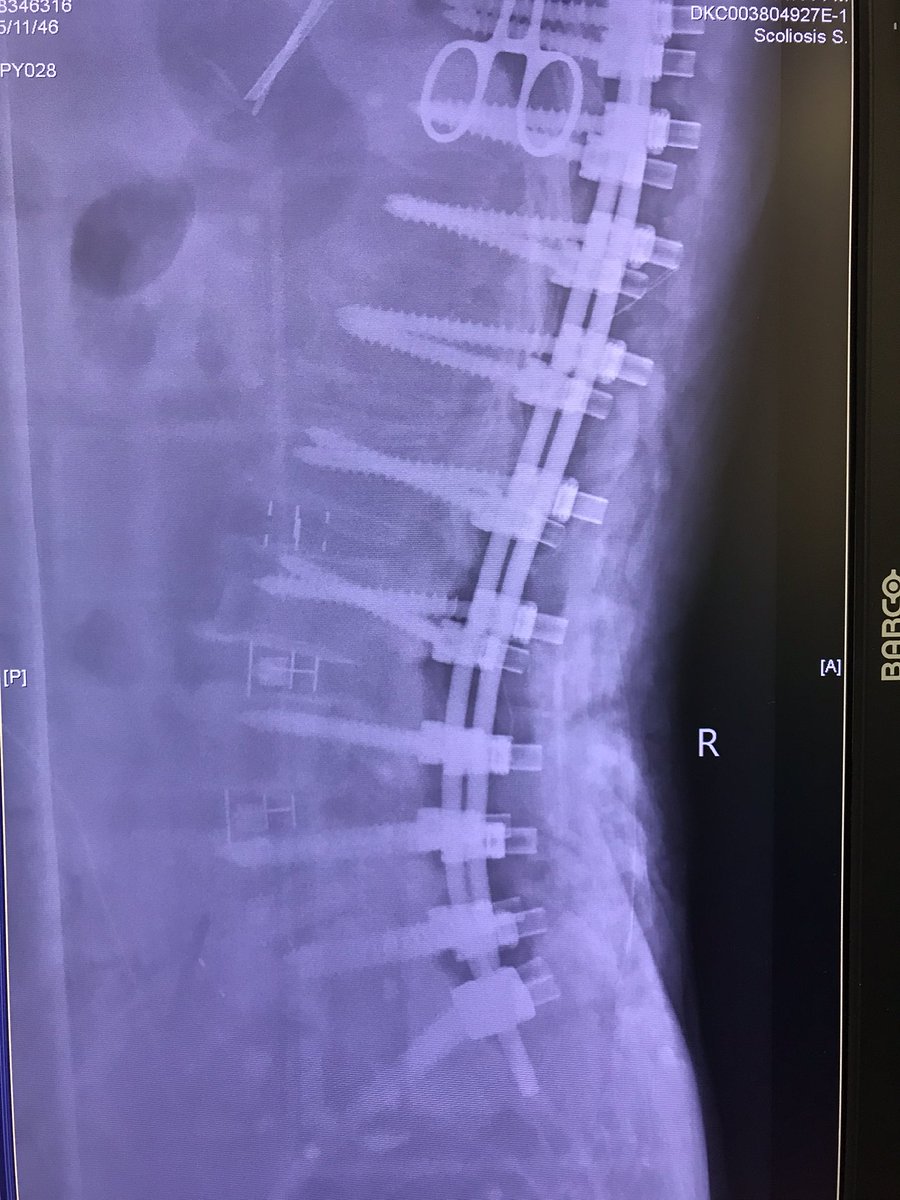

Good lordotic improvements

jasonpycheung's tweet image. Good lordotic improvements